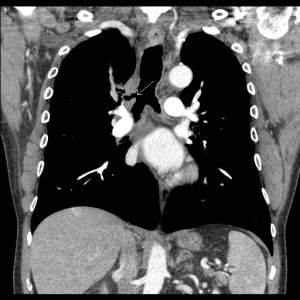

History: 60 year old male undergoing chest CT for follow up of a lung mass.

This anatomical variant is referred to as a tracheal bronchus. When the entire upper lobe is supplied by the accessory bronchus, it is called a pig bronchus. An excellent article summarizing these anatomical variants is present here. These variant bronchi are seen in about 0.1-2% of the population, and typically arise from the right side of the trachea. They place the patient at risk for recurrent pneumonia in the lobe supplied by the accessory bronchus.